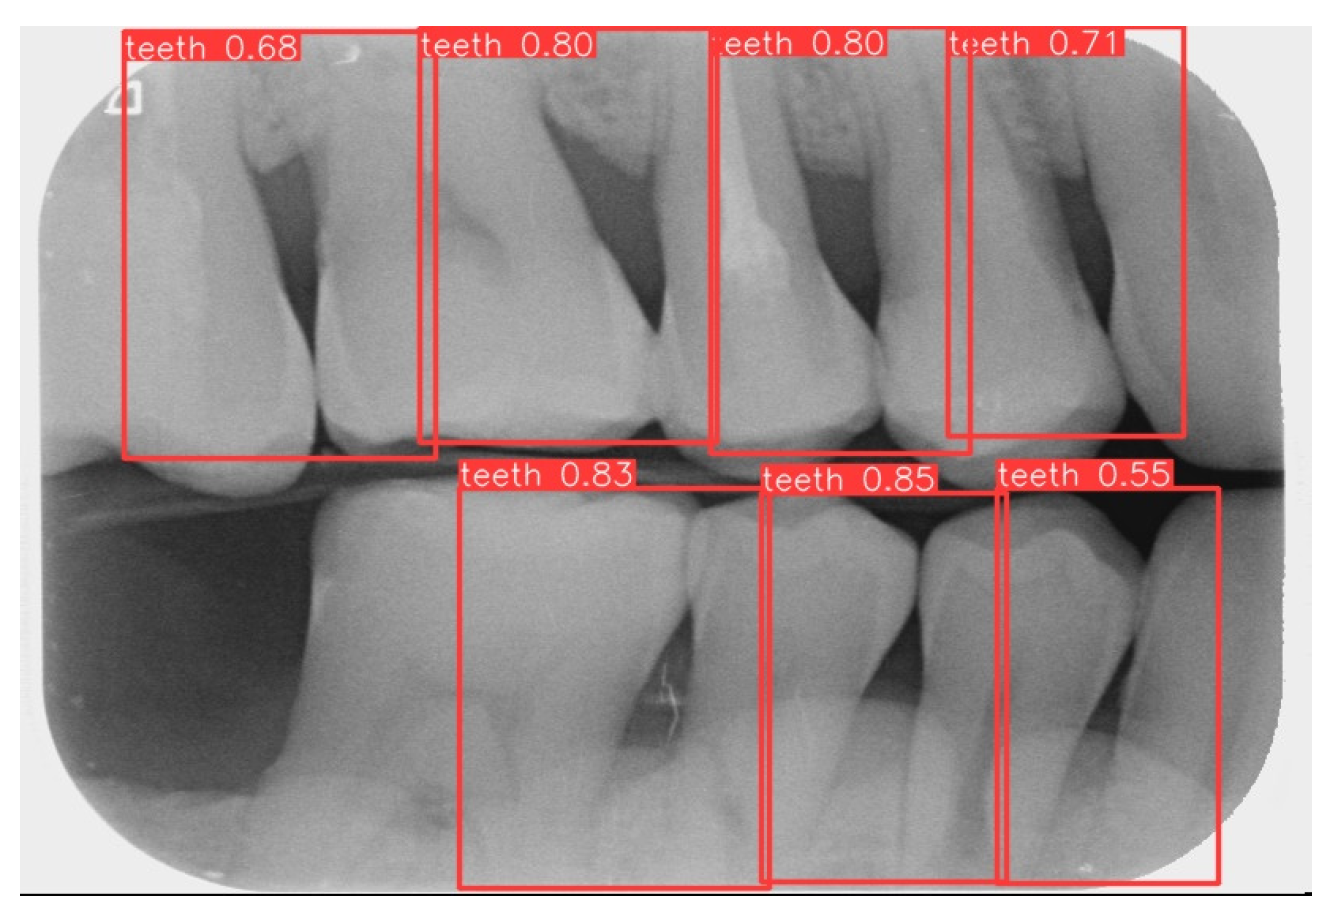

Labeling was used as a tool, and by utilizing the rectangular tool, the marking range was from a single tooth section to another tooth section, which helps to accurately mark the actual condition of the gingiva around the middle of the tooth. Finally, the image was saved as a YOLO file and labeled as shown in Figure 2a. This process highlights the target area in the image and provides clearer information for CNN training.

2.2.2. YOLOv8 Model Training

Numerous object detection models have been developed, such as the R-CNN series, Single Shot MultiBox (SSD), RetinaNet, and YOLO. Due to the complexity and variability in tooth alignment in each patient, the gums need to be separated at the BW film; YOLOv8 is the best model utilized in BW image segmentation for Angular Erosion. The YOLO model has an advantage in detecting the foreground and is highly efficient in considering the global information of the image and making judgments, and it also utilizes an anchor-free design. In the past, anchor frame detection was utilized to envelop various objects with predefined anchors. Regression adjustment was carried out through a series of operations, and the most accurate frames were retained using non-maximum suppression. Anchor-free detection predicts the center point of an object directly from the image to learn its location and size. This method helps detect objects with greater accuracy in various complex scenes, such as accurately locating teeth. Target detection of the vertical biting airfoil image is then performed by the trained YOLO model, as shown in Figure 2b.

This study uses YOLOv8 to detect the gingiva between each tooth and record its coordinates. The parameters are listed in Table 6. The final target detection results of this study are shown in Figure 8. The comparison between the YOLO detection model and other studies is presented in Table 7. The image shows that the gum features are completely preserved, providing a reliable basis for CNN.

Figure 2. Image annotation and segmentation. (a) Image Annotation Diagram. (b) The tooth segmentation result.

Figure 8. YOLOv8 detection result.